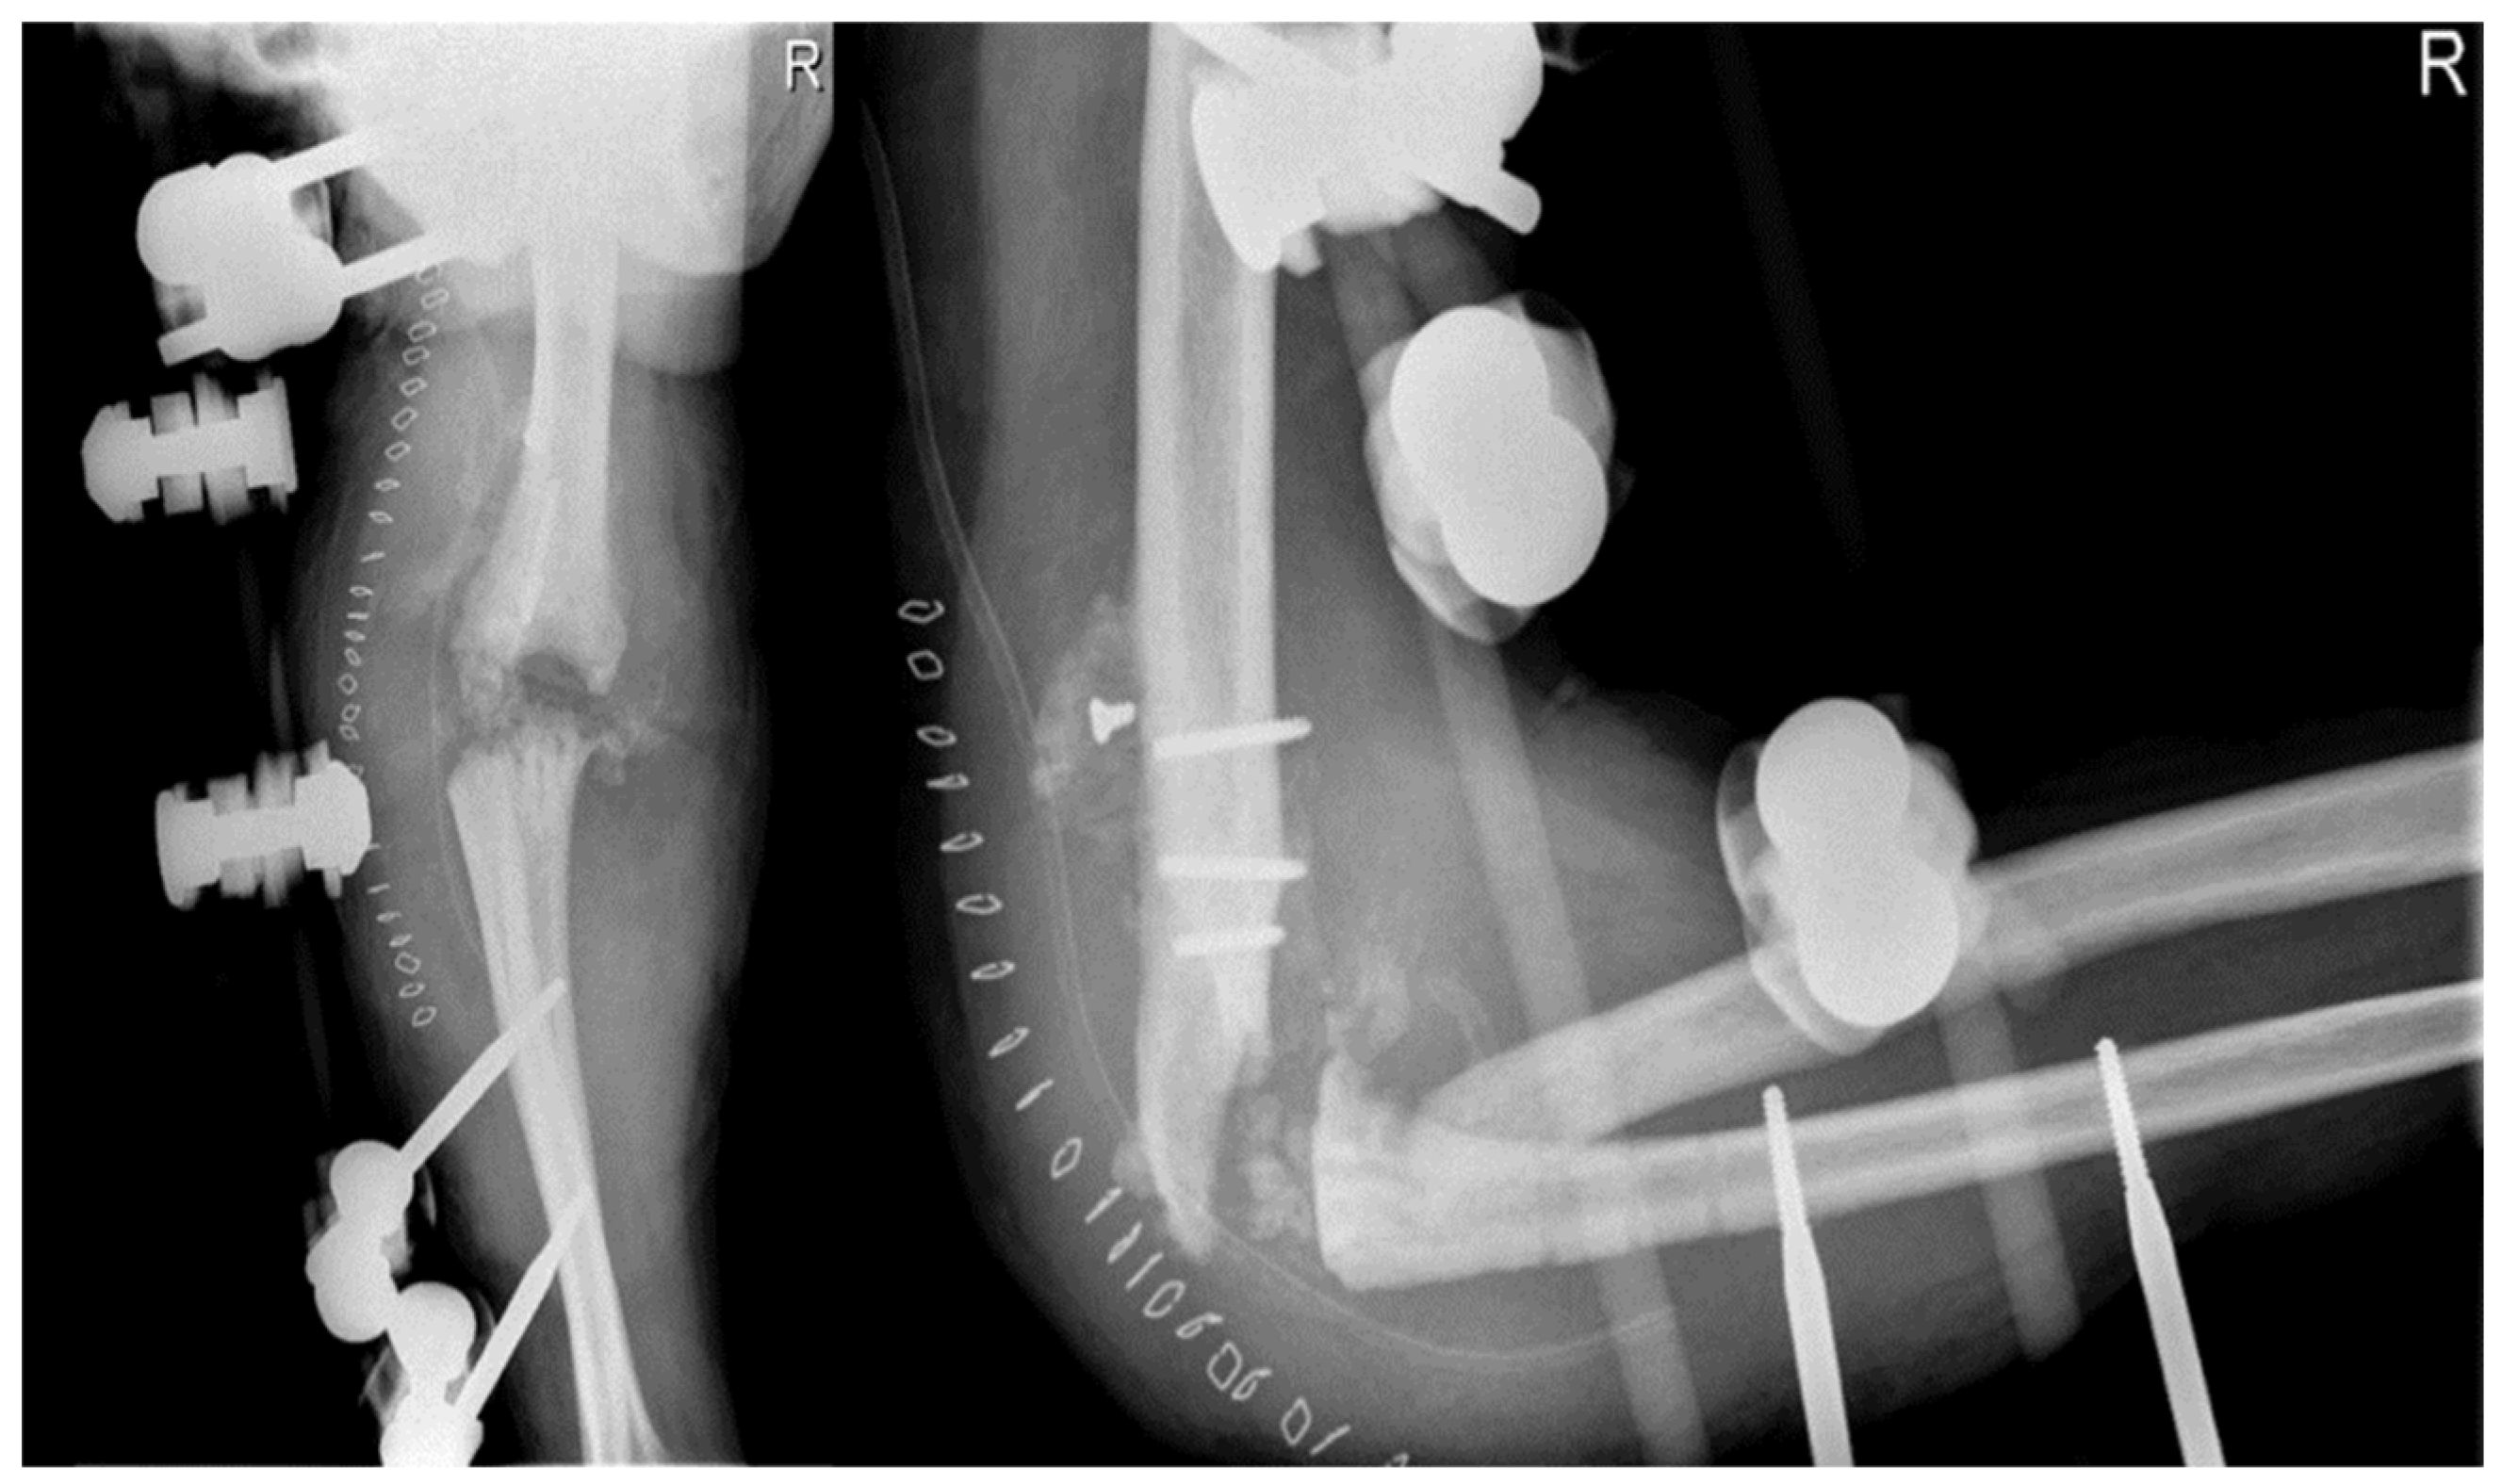

In early August 2013, a surgical procedure was performed to fuse the elbow joint using a plate with 12 holes and a 90-degree flexion angle, using the same surgical access point as the previous surgery (Figure 4). During the procedure, it was observed that the anatomical structures of the ulna, radial head, and distal humerus were severely distorted and not recognizable. A new synovectomy and osteotomy were performed to apply the plate. After discharge from the hospital, the patient was instructed to wear a brace at 90 degrees and an arm sling, undergo physiotherapy to mobilize the fingers and wrist, and have an X-ray examination 30 days after the surgery.

At the 30-day postoperative follow-up, X-rays revealed three broken screws in the proximal humeral shaft and a subtle periosteal reaction around the plate. The patient was provided with a new brace and referred for a fixation revision. The screws and plates were removed using the previous lateral elbow access from the surgery. The broken screw bodies and heads were left in place since they were embedded in the bone and soft tissue, respectively. However, due to the last 7 to 8 cm of the distal humerus appearing like a cortical lamina, internal fixation was not feasible. Consequently, an external fixator bar-to-bar was applied after the arthrodesis surfaces were prepared. A follow-up X-ray confirmed the device's appropriate positioning (Figure 5). At hospital discharge, the orthopedic recommendation was to wear the external fixator for 60 days, rest, and undergo weekly ambulatory assessments of the local clinical findings.

Figure 4. Post-arthrodesis X-Ray anteroposterior and lateral views of the right elbow. (a) Post operative images. (b) 30 days after images.